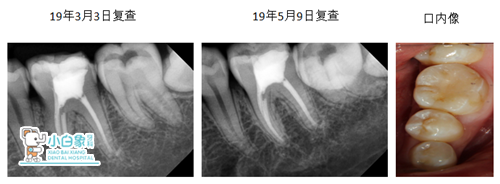

根尖暗影未见明显增大,在逐渐缩小

医嘱:及早冠修复。